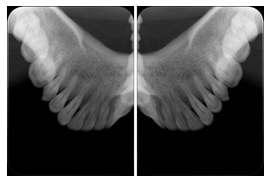

- OO-1. Intra-oral Full Mouth Series Structured Display